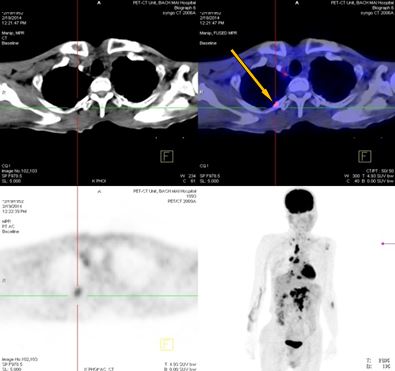

+ Vùng phế quản gốc phải có khối KT 2,4x1,7cm, tăng hấp thu F-18 FDG, max SUV=8,50. Hạch trung thất kích thước lớn nhất 3,1x3,5cm, max SUV=10,29

+ Hạch thượng đòn phải KT 1,1cm, tăng hấp thu F-18 FDG, max SUV=5,67; Hạch thượng đòn trái KT 0,8cm, max SUV=3,97. Tổn thương cung sau xương sườn số 2 bên phải tăng hấp thu F-18 FDG, max SUV=3,13.

Trước điều trị: Hạch thượng đòn phải 1,1cm, max SUV=5,67; Hạch thượng đòn trái 0,8cm, max SUV=3,97.

Sau điều trị: Không thấy hạch thượng đòn